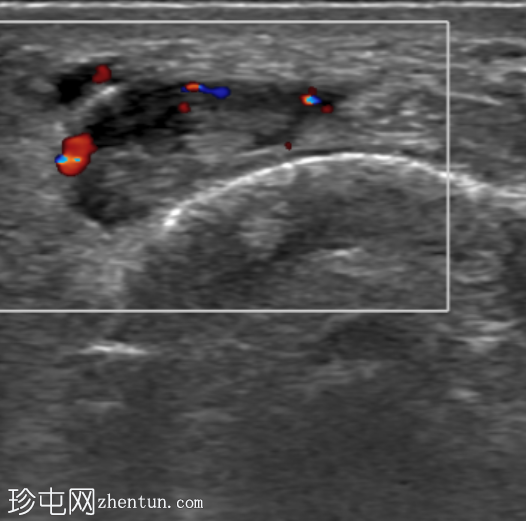

超声

横切面

第一背侧伸肌腱鞘增厚。拇长展肌 (APL) 和拇短伸肌 (EPB) 肌腱周围可见低回声液体。受累肌腱轻度增厚。未见肌腱撕裂。邻近皮质表面完整。多普勒显示轻度血流信号增多。